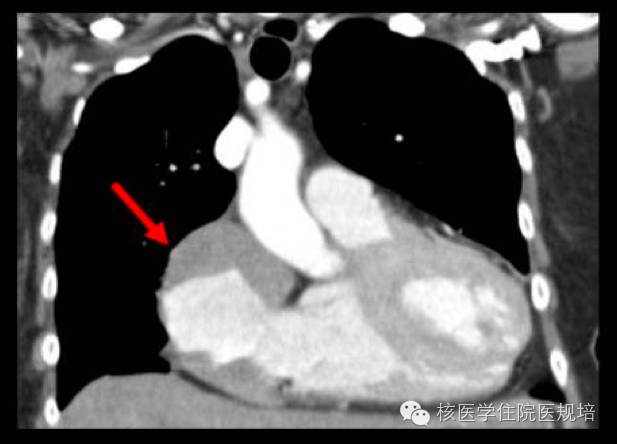

整体观察见MIP图(图3)。主要阳性发现包括:左心房、主动脉及肺动脉主干周围可见环形、弥漫性FDG摄取(SUVmax 3.8),但相应部位平扫CT未见明确异常结构改变(图4);右肾盂扩张,内见形态不规整FDG摄取增高软组织密度肿物影(SUVmax 4.9),边缘毛糙,范围约3.6 cm×2.9 cm×3.0 cm,并包绕上段输尿管,同时见右肾盂积水(图5);四肢长骨FDG摄取对称性增高(SUVmax 3.2),自关节端向骨干伸,相应部位CT见不规则骨质硬化,其中右股骨内侧髁可见溶骨性骨质破坏(图6);脊柱及骨盆亦可见多发性质类似的骨病变(图7、8)。

图4. 左心房、主动脉及肺动脉主干周围可见环形FDG摄取

ECD心血管系统受累约占75%,以心包受累常见,导致心包增厚及心包积液。组织细胞还可浸润心肌,常表现为以右房及房室沟处假瘤样软组织浸润影(图11)。出现心肌受累者往往提示预后不良,可发生心肌重塑、瓣膜功能障碍,最终死于心力衰竭等并发症。冠脉及大血管管壁可因组织细胞浸润发生纤维化,最终出现动脉狭窄,靶器官缺血。影像上大动脉周围软组织浸润可形成“动脉鞘”,可自升主动脉至髂动脉分叉处阶段性或弥漫性累及(图12)。

本例患者尽管平扫CT未见明显结构异常,但左心房及大血管周围异常FDG摄取带在增强CT扫描下可能会更清晰地显示出相应病变。